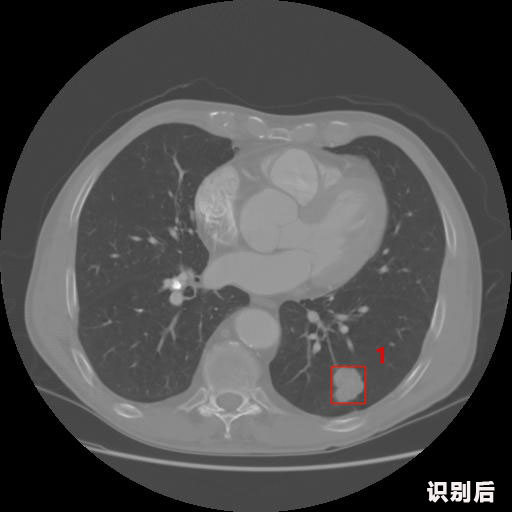

報(bào)告:

1.發(fā)現(xiàn)肺結(jié)節(jié)的可能性為95.56%---位于框指數(shù)位置:[331.70554 366.13406 365.21707 403.96234]